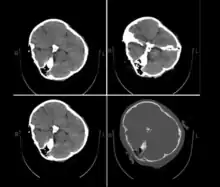

Published hospital pictures show Mahsa Amini bleeding from the ear and with bruises under her eyes. In an 18 September letter, Doctor Hossein Karampour (the top medical official in Hormozgan province), pointed out that such symptoms "do not match the reasons given by some authorities who declared the cause to be a heart attack... (they are instead consistent with) a head injury and the resulting bleeding."[64] This was also confirmed by alleged medical scans of her skull, leaked by hacktivists, showing bone fracture, hemorrhage, and brain edema.[10][65]

Low-res copy of Amini post-arrest CT scan allegedly leaked to Iran International

By 21 September, the hospital had released preliminary CT scans. Government supporters stated the CT scans showed psychological stress caused by a previous brain operation; critics stated the scans showed physical beating and trauma. The Iranian government stated Amini had a brain operation at the age of five.[67]